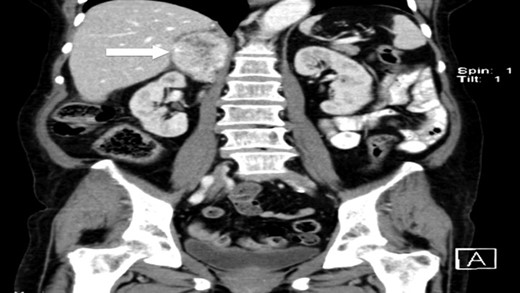

The authors report a case of a 64-year-old female, with no relevant family history and a past medical history of recently diagnosed supraventricular tachycardia, arterial hypertension, type 2 diabetes mellitus, euthyroid multinodular goiter and chronic venous insufficiency. She was referred to our Institution from other Hospital where she went due to paroxysms of palpitations, headache and diaphoresis, that led to biochemical investigation that was remarkable for: total plasmatic cathecolamines: 73 747 ng/L (normal range (NR) <598 ng/L), plasmatic noradrenaline: 73 589 ng/L (NR <420 ng/L), adrenaline: 130 ng/L (NR <84 ng/L), plasmatic dopamine: 28 ng/L (NR <94ng/L), aldosterone: 87,5 ng/dL (NR 4–31 ng/dL), plasmatic renin activity: 33 ng/mL/h (NR 0,5–4 ng/mL/h), Vanylmandelic acid: 39,2 mg/24 h (NR <13,6 mg/24 h). Abdominal contrast enhanced CT scan revealed a large (70 × 35×78 mm3), hyperdense (20 HU) right adrenal mass. Abdominal magnetic resonance (MRI) also described an adrenal mass with 66×33 mm2, suggestive of pheocromocitoma (slightly hypointense on T1 and markedly hyperintense on T2 weighted imaging). No vascular nor locoreginal lymph node involvement were found and the left adrenal was radiologically normal. The patient underwent genetic testing with next generation sequencing, that excluded mutations of the succinate dehydrogenase (SDHB, C, D and A), MEN2, VHL, Neurofibromatosis type 1 genes. Genetic testing for MAX and TMEM127 were not performed due to institutional unavailability. Pre-operative pharmacological therapy was initiated with phenoxybenzamine (10 mg twice a day), followed by bisoprolol (20 mg/day) and amlodipine (5 mg/day), which rendered the patient fit for surgery. The patient underwent transperitoneal laparoscopic right adrenalectomy. Intraoperatively, a hipervascularized right adrenal gland with adhesions to the upper pole of the kidney was identified and excised, with no complications recorded. In the immediate post-operative period, antihypertensive drugs were stopped and blood pressure remained normal until the second post-operative day, when hypertension and tachycardia recurred, leading to urinary metanephrine reevaluation on the 10th post-operative day. The results were highly suggestive of disease persistence (urinary normetanephrines >10 500 ng/L (NR <600 ng/L)). Histology revealed no signs of neoplasia. Abdominal CT scan revealed the persistence of a solid heterogeneous nodule, with 70 × 49 × 87 mm3 (AP × T × L) adjacent to upper right renal pole, with peripheral contrast enhancement and central necrosis (Figs 1–3). This findings suggested abdominal paraganglioma (of the organ of Zuckerkandl). Due to the higher malignant potential of paragangliomas, an 123I-MIBG scintigraphy was performed, excluding metastatic disease.

CT scan (coronal) of the heterogenous solid nodule adjacent to upper inner right renal pole (white arrow).